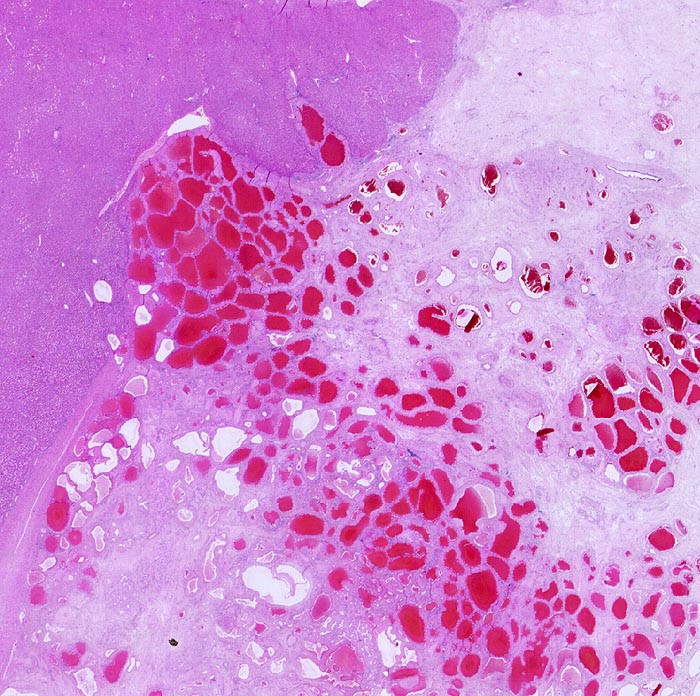

AP/ Hämangiom

Hämangiom

benigner Tumor

Leber, Gallenwege, Pankreas

Leber